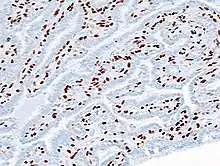

| Histopathology of intraductal papilloma of the breast by excisional biopsy. Immunostaining for p63 protein. | |

Histopathology of intraductal papilloma of the breast by excisional biopsy. Hematoxylin and eosin stain.

Histopathology of intraductal papilloma of the breast by excisional biopsy. Immunostaining for alpha-smooth muscle actin.